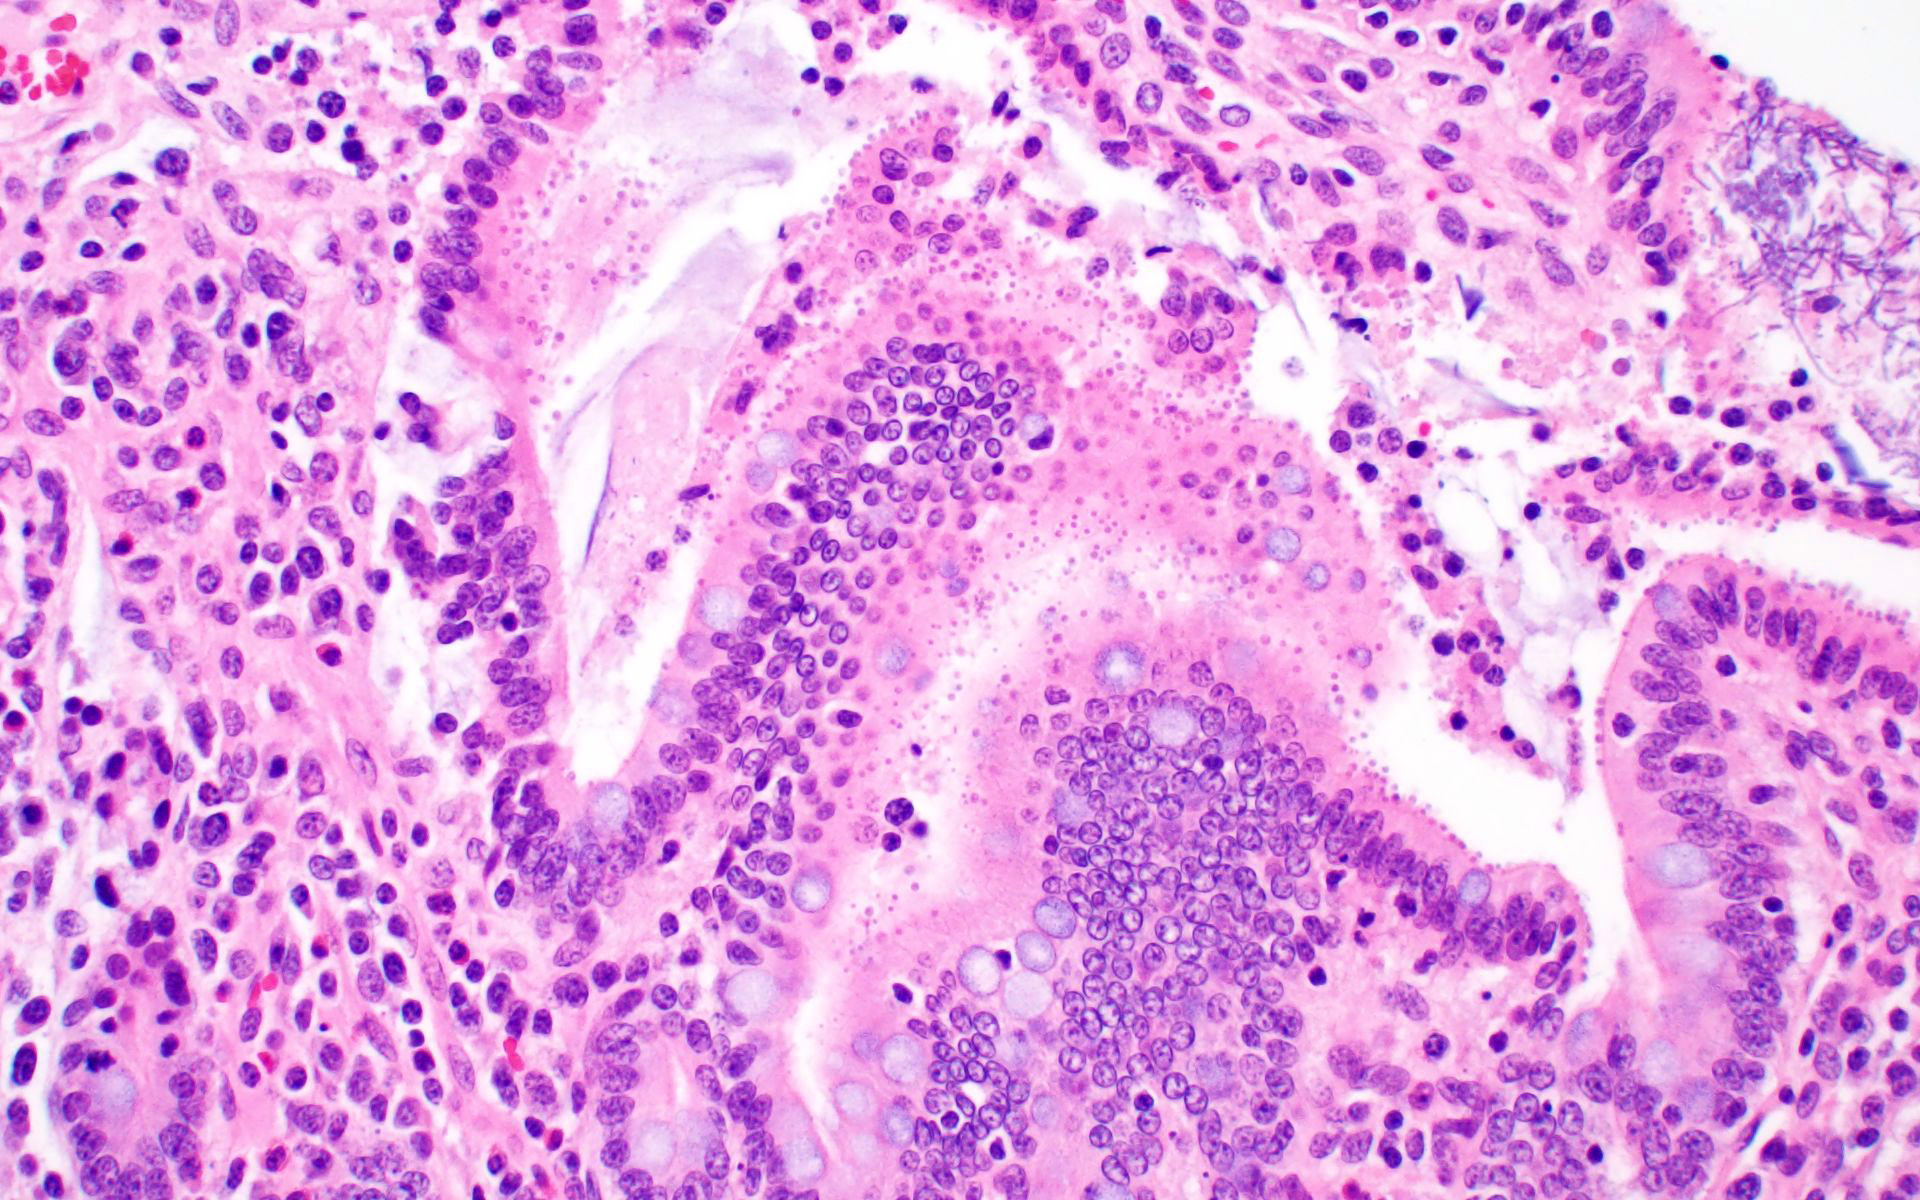

Ileum: In several sections, there is moderate multifocal blunting and fusion of villi with a crypt: villus ratio of 1:1. Apical enterocytes are often moderately attenuated with loss of the brush border and reduced apical cytoplasm. In some sections, these cells have a profound number of intracellular but extracytoplasmic 1-2 um circular eosinophilic apicomplexan organisms with 0.5 um basophilic nuclei (Cryptosporidium sp.). In other sections, these cells contain numerous larger apicomplexans with varied life-stages apparent including: 10 x 5 um curvilinear binucleate meronts (type I meronts), 4 x 12 um curvilinear uninucleate merozoites (type I merozoites), 9 x 6 um ovoid multinucleate meronts (type II meronts), multiple 3 x 12 um curvilinear uninucleate merozoites joined at their base by a residual body (type II merozoites), a 12um diameter circular lightly basophilic microgamont filled with numerous peripheral uninucleate deeply basophilic microgametes, or a 18 um diameter circular lightly basophilic macrogamont with a 8 um granular circular nucleus (macrogamont) (Cystoisospora suis). Rare crypts are ectatic, lined by moderately flattened, attenuated epithelium, and filled with cellular and karyorrhectic debris admixed with rare degenerate neutrophils (crypt abscesses). The associated lamina propria is often infiltrated by numerous eosinophils admixed with a few neutrophils. In one section, there is profound necrosis in Peyer’s patches, characterized by abundant karyorrhectic and cellular debris admixed with rare neutrophils, that often obscures typical follicular architecture. Similar changes are occasionally present in the overlying lamina propria, with marked lymphocytolysis and loss of proprial architecture. Vascular structures in all tunics are moderately congested, and macrophages occasionally aggregate around medium-caliber vessels in the submucosa.Spiral Colon: In both sections, there is moderate multifocal ulceration of the colonic mucosa characterized by loss of apical colonocytes with abundant cellular and karyorrhectic debris admixed with minimal fibrin and extravasated erythrocytes adhered to the exposed lamina propria. Adjacent colonocytes are often flattened, irregularly spaced, with reduced apical cytoplasm (attenuation). The associated lamina propria is often infiltrated by neutrophils and eosinophils admixed with necrotic debris and a few macrophages. Crypts within these areas are often ectatic, lined by mildly attenuated epithelium, and filled with either cellular and karyorrhectic debris admixed with degenerate neutrophils (crypt abscesses) or numerous eosinophils. Several other crypts are filled with up to 15 5 x 7 um pyriform to crescent-shaped protozoa with lightly basophilic cytoplasm and a faint nucleus (Suspect Trichomonads). The colonic lumen contains abundant cellular debris admixed with numerous colonies of basophilic bacteria with morphology ranging from coccoid to bacillary to filamentous, as well as rare 80 um circular flagellated protozoa with a prominent bean-shaped nucleus and a large cytoplasmic vacuole and abundant phagocytosed cellular debris (Suspect Balantidium coli). The submucosa is multifocally infiltrated by numerous macrophages admixed with lymphocytes and a small amount of karyorrhectic debris and these cells often aggregate around medium to large caliber vessels. Multifocally the cortical and medullary architecture of the mesenteric lymph node is effaced by abundant cellular and karyorrhectic debris (lymphocytolysis) admixed with rare infiltrating neutrophils and macrophages.

Ileum and colon (mediastinal lymph node, Peyer’s patches, and lamina propria): Lymphoid necrosis, multifocal, profound, subacute.Ileum: Atrophic enteritis, necrosuppurative and eosinophilic segmental, marked, subacute, with crypt abscesses and numerous intralesional apicomplexans with morphology consistent with Cryptosporidium spp. and Cystoisospora suis

- Ileum: Villar blunting, diffuse, marked with numerous intracytoplasmic, extracellular apicomplexan schizonts and gamonts consistent with Cryptosporidium sp., and intracytoplasmic, intracellular apicomplexan meronts, schizonts, and gamonts consistent with coccidiosis.